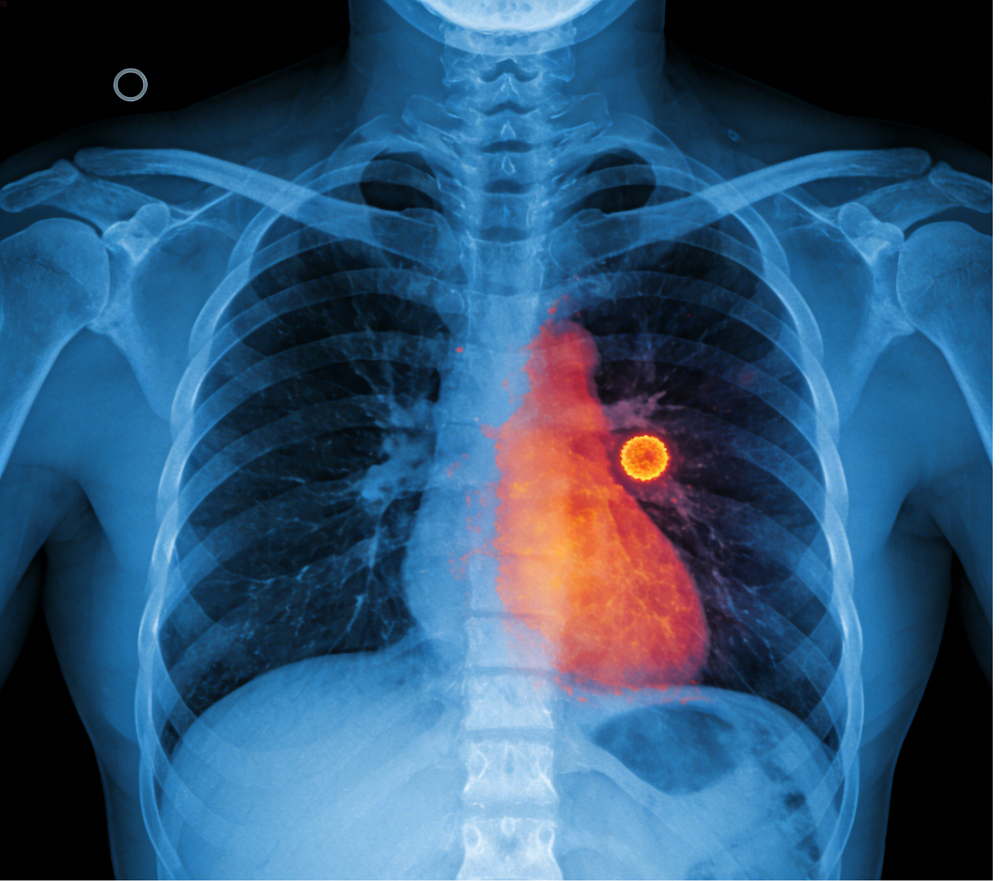

在CT影像上,直径≤3厘米的圆形、类圆形或局部密度增高的影子,都可以称为肺结节,多数为良性。研究表明,结节越大,恶性风险越高,6毫米以内的肺结节恶性概率小于1%。具备毛刺、分叶、胸膜牵拉、血管集束、不典型钙化、直径>8mm或随访增长等特征的高危肺结节,可能是早期肺癌的表现。

如果体检报告中显示肺结节有毛刺征、分叶状、血管集束征、胸膜凹陷征等特征,那可能很危险。